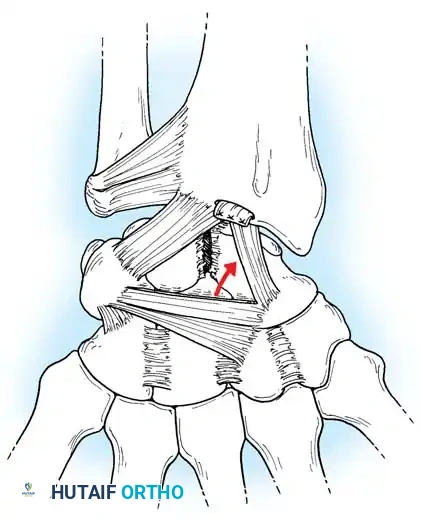

Fig. 66-76 Radioscaphoid ligament (RSL) and surrounding capsular anatomy.

Closed reduction with percutaneous pinning (placing 0.045-inch K-wires from the scaphoid to the capitate and lunate) can be attempted. However, open reduction through a dorsal approach is generally preferred. This allows direct closure of the scapholunate gap, K-wire fixation, and primary repair of the dorsal SL interosseous ligament using suture anchors.